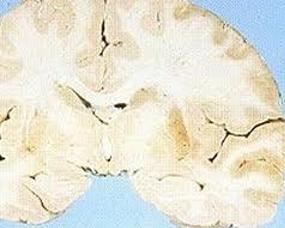

多发脑梗死性痴呆(multi-inrctdementia,MID)由精神病学家Hachinski(1974)提出,是血管性痴呆(VaD)最常见的类型,占39.4%。因为频频发生卒中,双侧半球大脑中动脉或后动脉多个分支供血区的皮质、白质或基底核区受累。导致智能及认知功能妨碍分析征,是老年性痴呆的常见病因之一。多发性脑梗...

多发性脑梗死是指脑内有多个缺血性软化梗塞灶而言,又称为多发性脑软化。除常见的瘫痪、感受与言语妨碍外,还可能呈现痴呆。大夫们就将这种痴呆称为多梗塞性痴呆(即动脉软化性痴呆)。多发性脑梗死好发于50-60岁的男性,高血压以及动脉软化是次要病因。食物多样,谷类为主;多吃桃、橙、香蕉、菠菜...